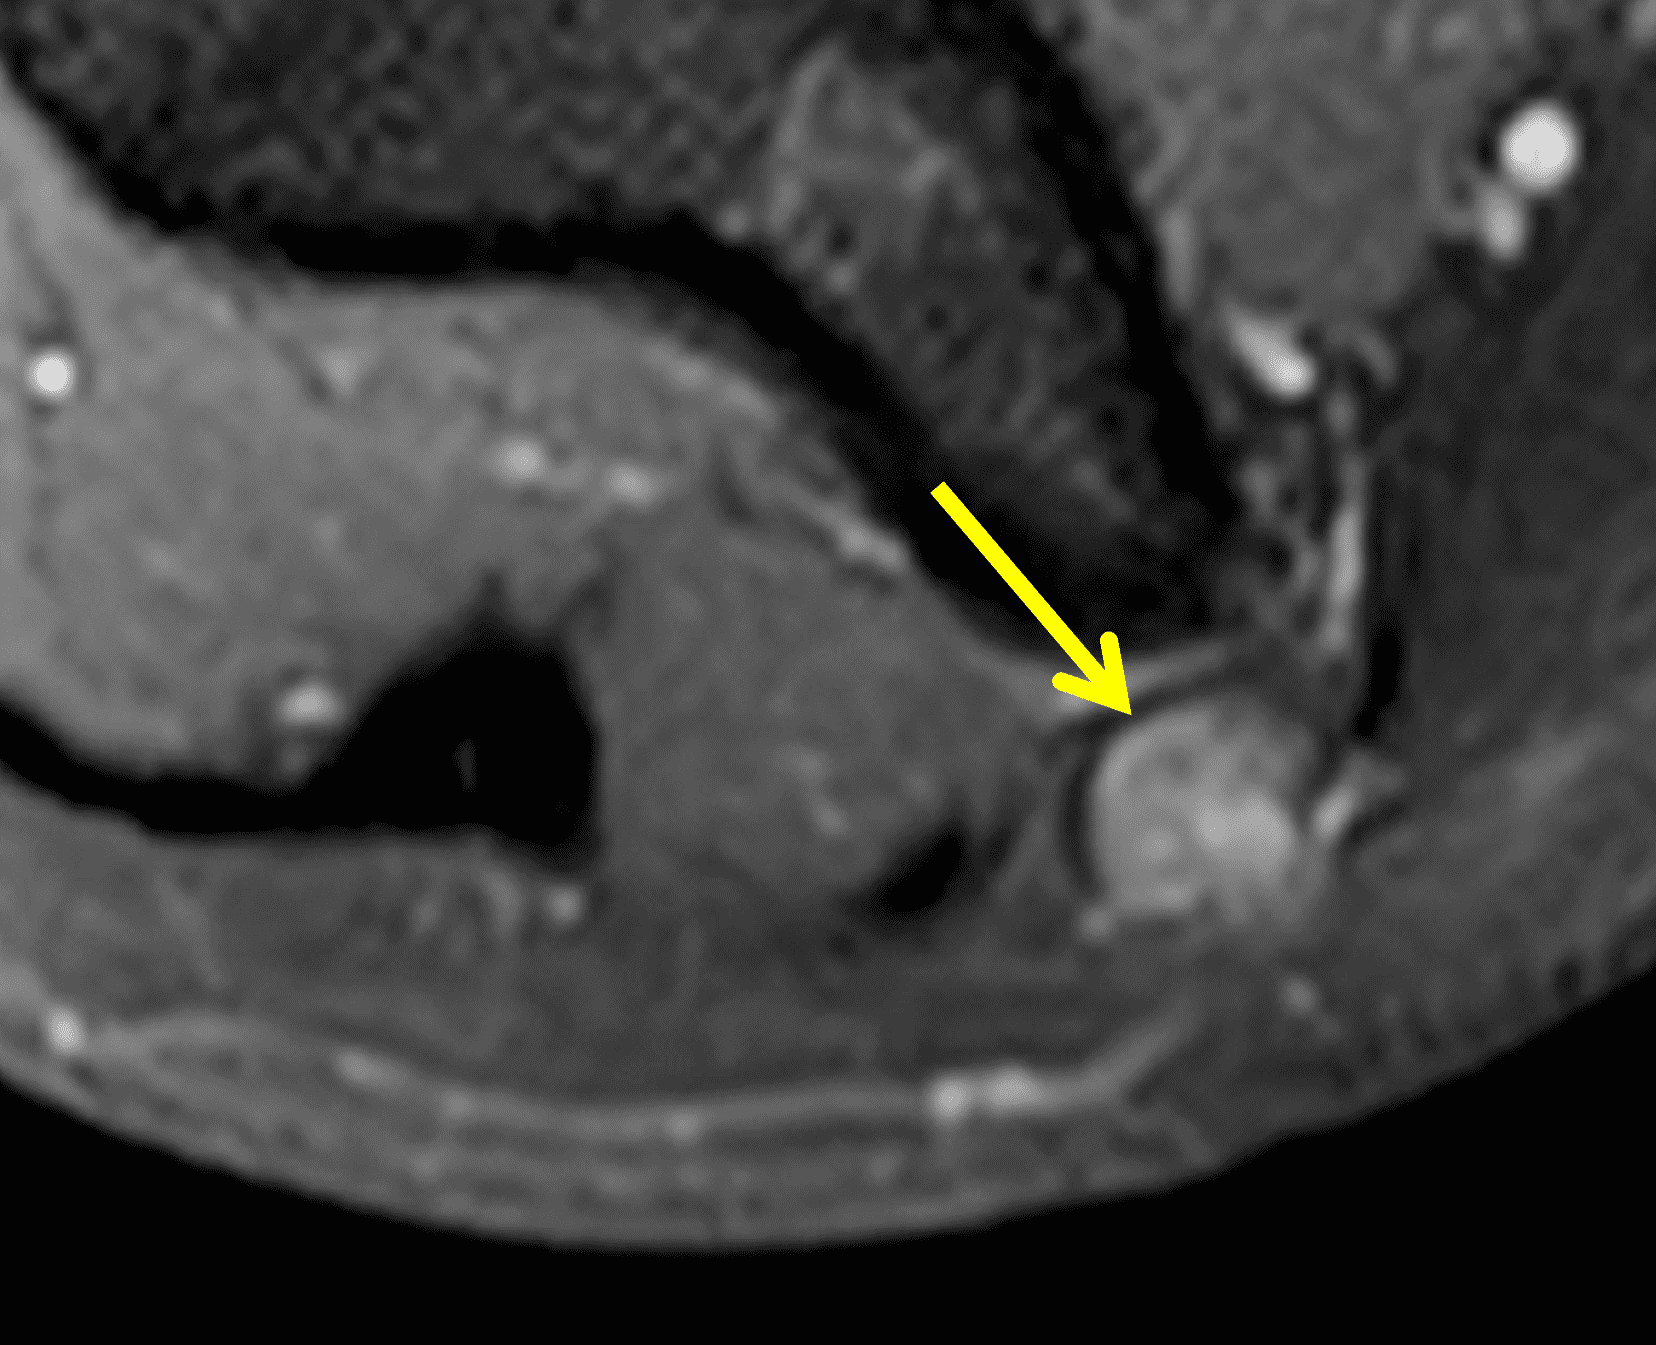

Figure 12: 16-year-old girl who reports a “snapping” sensation with elbow flexion. She has no neurologic symptoms. Axial (12A) T1-weighted and (12B) fat-suppressed, fluid-sensitive images with the elbow extended show the ulnar nerve (arrows) normally located within the cubital tunnel. The retinaculum is either hypoplastic or absent. With elbow flexion, (12C) T1-weighted and (12D) fat-suppressed, fluid-sensitive images show the ulnar nerve (red arrows) dislocated medial to the medial humeral epicondyle. Note that a portion of the medial triceps muscle (yellow arrows) is also subluxed.